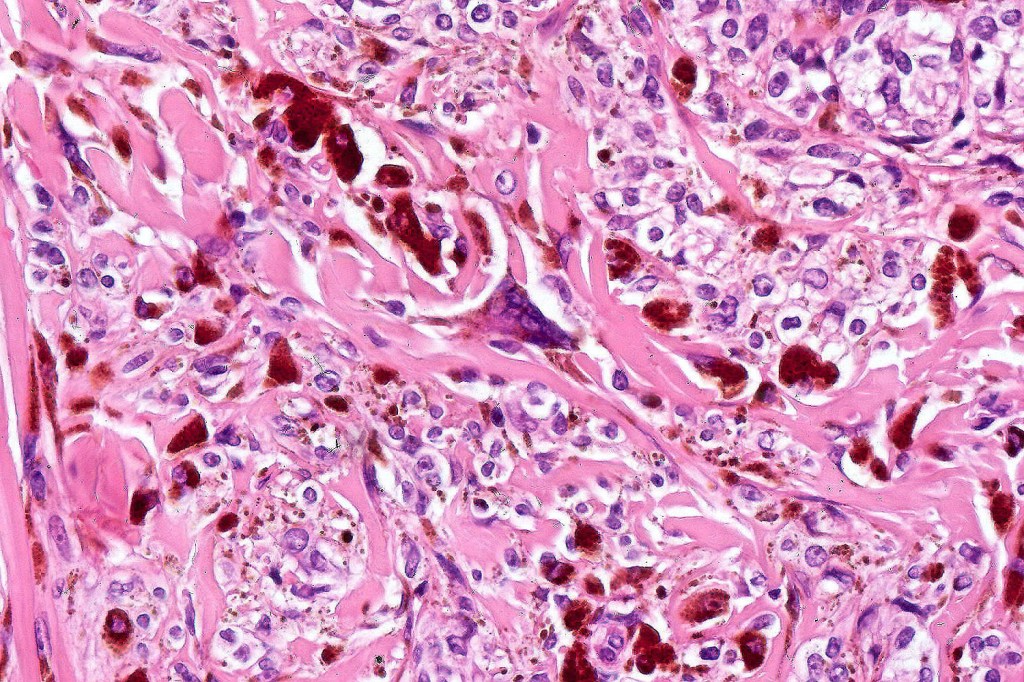

•Admixture of spindle cells, pigmented bipolar or dendritic cells & melanophages

•Cytoplasm is pale and nuclei are small with inconspicuous nucleoli

•An alveolar pattern is characteristic particularly with clear cell nodules

•No Necrosis or lymphovascular invasion

•Stromal fibrosis, myxoid change, vascular hyalinization with cyst formation are often seen